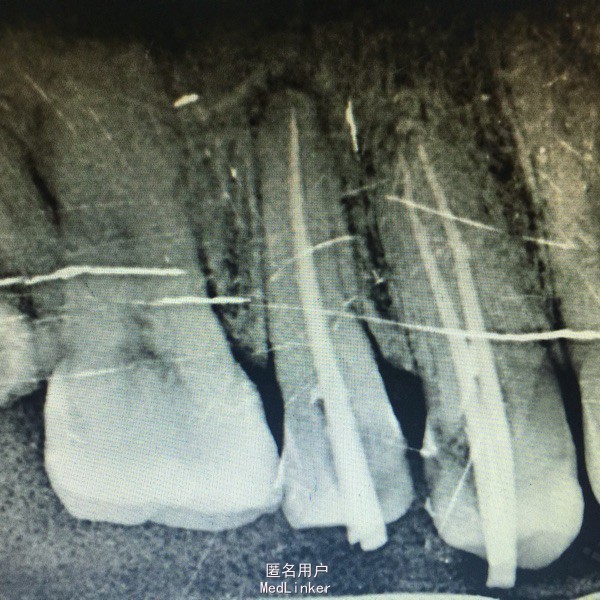

查体:14,15邻面之间龋坏,洞底有大量软化牙本质,探(+),冷热诊疼痛明显且持续较长时间。叩(-),X线示龋坏深达牙髓腔。17,37残冠,26牙合面大面积龋坏,探(+)冷(+)叩(-),X线示龋坏深达髓腔。 患者血压,血糖在正常范围,其余满足拔牙适应症。

诊断:14,15,26牙髓炎17,37残根 治疗: 局麻下14,15去腐,开髓揭髓顶降牙合,冲洗髓腔,拔髓疏通根管,测量根管配合EDTA进行根管预备,次氯酸钠进行根管冲洗,吸潮纸尖拭干根管,进行根管试尖,X线示恰充,进行热牙胶垂直加压连续波充填法进行根管充填。暂封观察进行树脂嵌体修复。分次拔除17,37.嘱拔牙后注意事项。